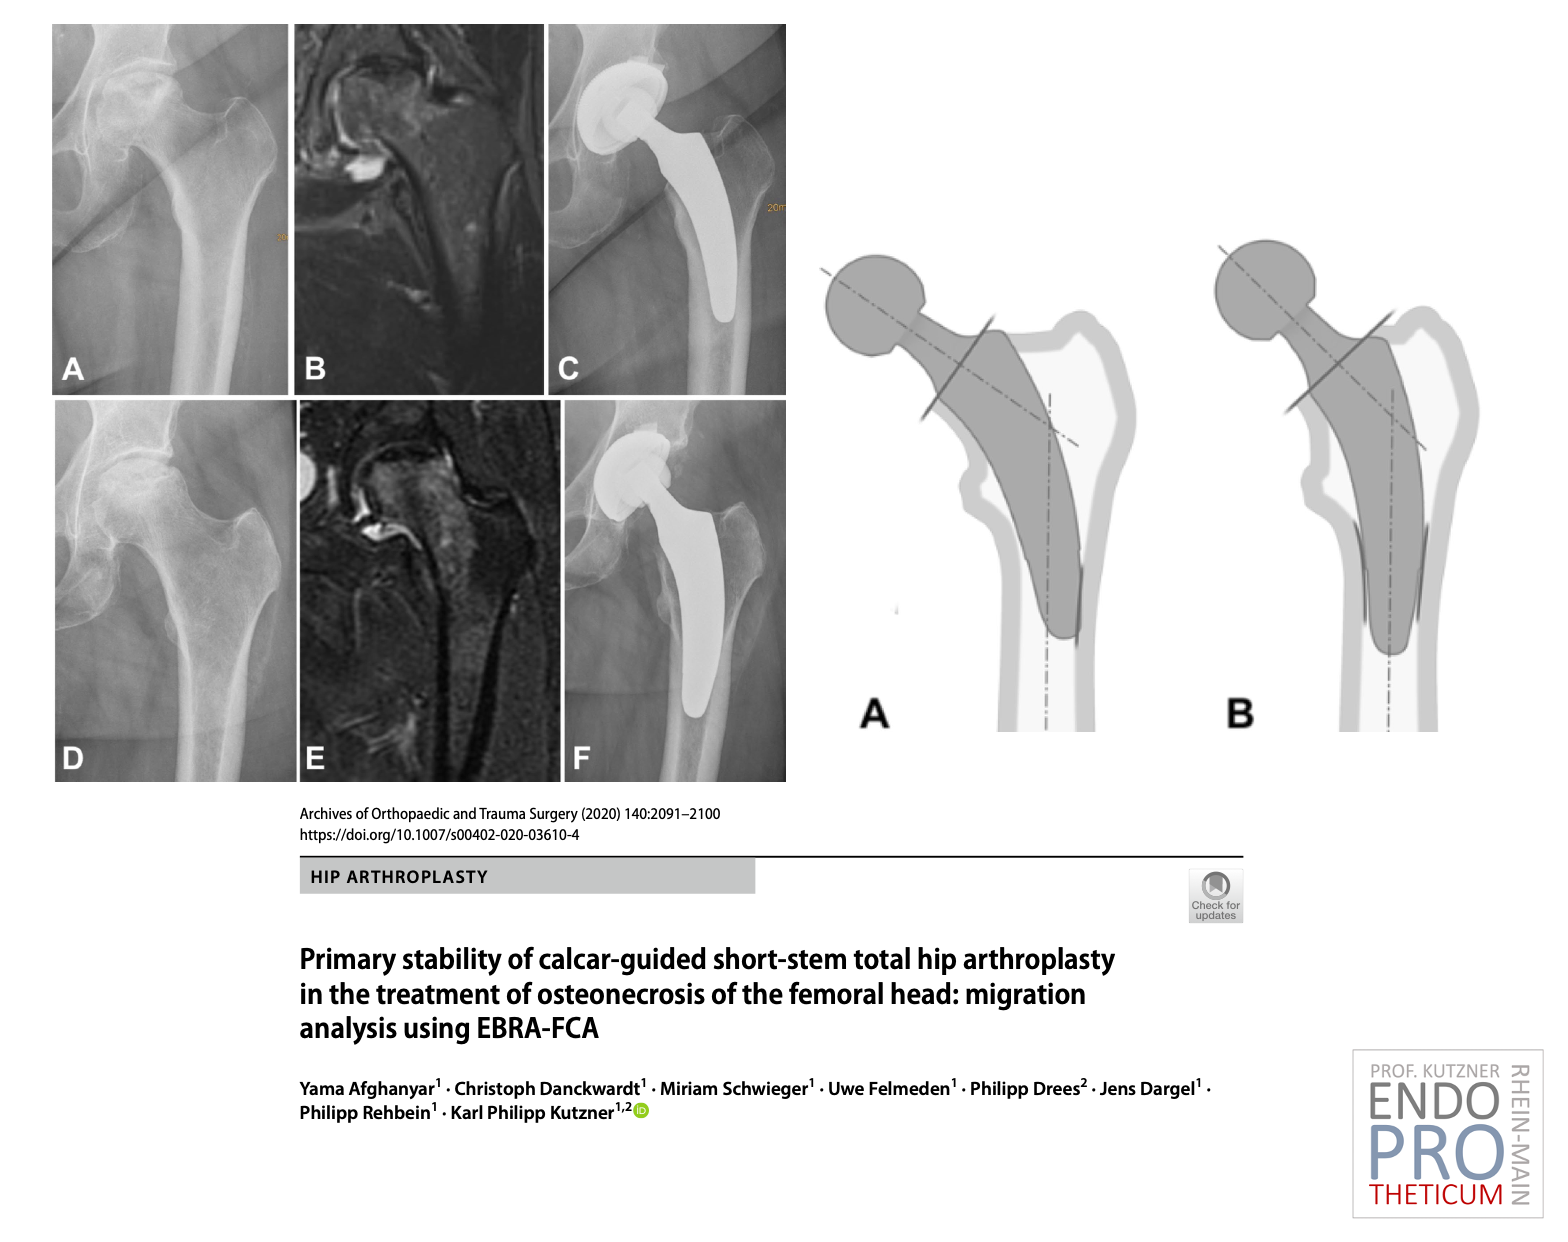

The concept of modern calcar-guided short stems in hip arthroplasty aims at the precise reconstruction of the individual, anatomical hip geometry. A bone and soft tissue-sparing implantation technique is used in conjunction with a physiological load in the part of the femur near the joint in order to preserve the bone in the long term.